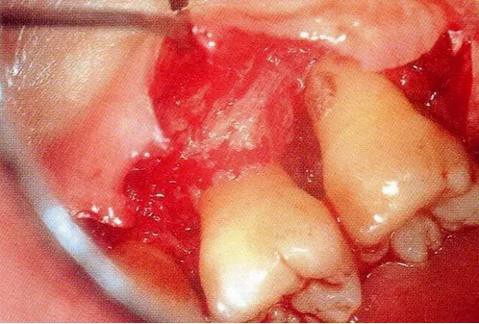

▼圖13-2 將齦溝切開,盡可能保存牙齦組織的情況下做翻瓣形成。確認有根面牙結(jié)石。

▼圖13-3 廓清處理結(jié)束的狀態(tài)。觀察到存在圍繞著顎側(cè)根擴展開的骨缺損,之間存在2壁性骨缺損。